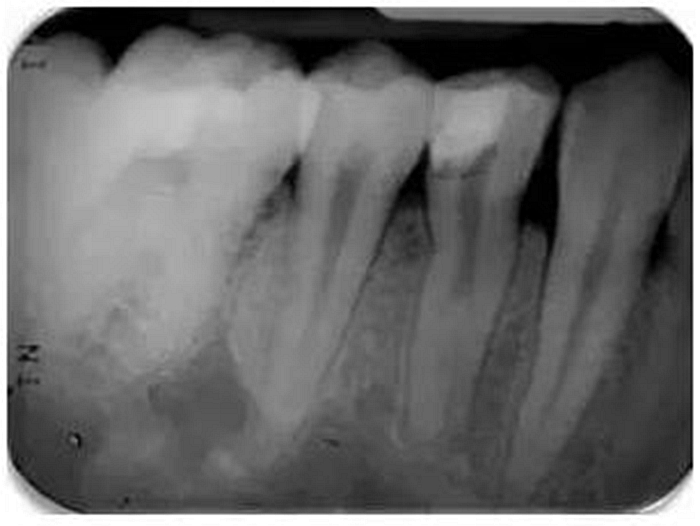

根尖周X線片必須要有最小的失真率和放大倍率,因?yàn)槿魏紊扉L和透視縮短都會導(dǎo)致根管長度測量的錯(cuò)誤。對牙根進(jìn)行仔細(xì)的評估是必不可少的,因?yàn)榭赡苡谢窝栏▓D1)。在中國患者中發(fā)現(xiàn)C形根管或其他蒙古人種特征的畸形牙根和根管是很常見的。因此,對X線片進(jìn)行全面評估以確定是否存在額外的牙根或根管是必要的,由此我們可以判斷治療的難度系數(shù)。